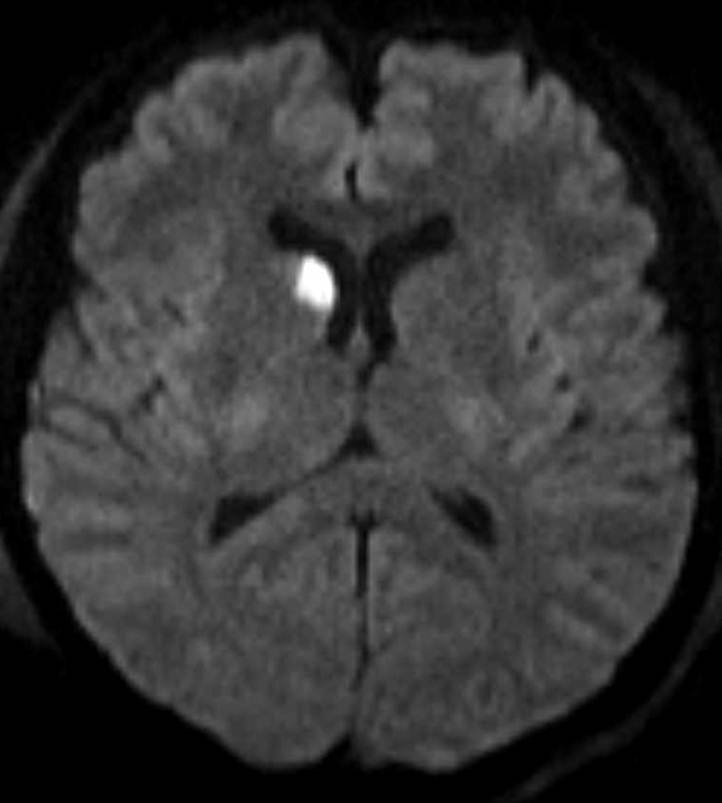

Neurologic examination revealed a complete left sided oculomotor lesion. Besides that no focal neurological signs were present. She was sedated and intubated at the emergency department and transferred to the Neurological Intensive Care Unit (NICU). Admission MR-angiogram showed bilateral dissection of internal carotid artery ranging from bifurcation up to intracranial region (Figure1, Figure 2). Intravenous heparine was started. On day 3 after admission, control MRI diffusion weighted images showed multifocal lacunar infarctions frontoparietal bilateral, in the right ncl. caudatus and in the corpus callosum. (Figure 3)